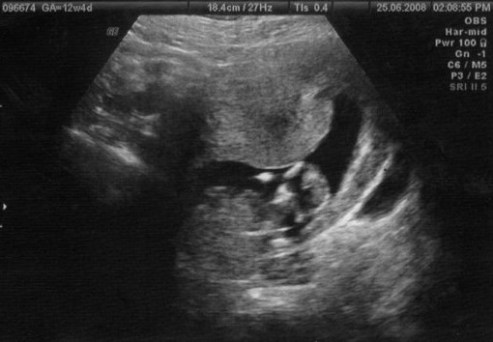

This is exactly what I encourage my clients to do – use their brain and ask intelligent questions. Think of a simple procedure like the Nuchal Translucency ultrasound most women have around 12 weeks and ask the 4 simple questions.

- Do you really need this procedure? This is a test that screens for Down Syndrome and other chromosomal abnormalities. For most women this is the first chance to have a look at their baby and they jump at the chance to do so. But do you really need this procedure? Will you abort a baby with Down Syndrome? If the answer is no then this is not a necessary procedure for you.

- What are the downsides? If the test indicates abnormalities, you will undoubtedly feel anxious and worried about your baby. The test generally used to confirm any issues is the amniocentesis which is a much more invasive and painful procedure with higher potential risks. So if you agree to the non-invasive NT test, you may find yourself in a position where you are forced to choose to undergo an amniocentesis to alleviate the stress brought on by the first test.

- Are there simpler, safer options? This test is already pretty safe and simple.

- What happens if you do nothing? If your baby is fine, then he will continue to be fine. If your baby has chromosomal abnormalities, he will continue to have chromosomal abnormalities. So this test only affects your peace of mind. It’s up to you to decide if knowledge is power or if you would prefer to stay ignorant.